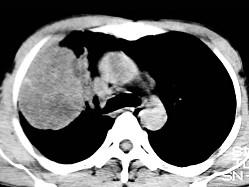

根据所提供的图像,选择最可能的诊断 ( )A、机化性肺炎B、局限性不张C、胸膜间皮瘤D、球形肺炎E、肺内软骨肉瘤

问题 根据所提供的图像,选择最可能的诊断 ( )

选项 A、机化性肺炎 B、局限性不张 C、胸膜间皮瘤 D、球形肺炎 E、肺内软骨肉瘤

答案 E